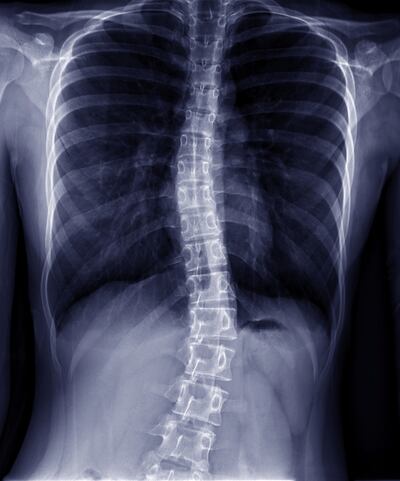

The most important thing with scoliosis is what caused it, he says. About 80 per cent of cases are idiopathic, “otherwise-well children who just happen to have scoliosis”, he explains. “But a small number have causes such as brain tumours or spinal cord tumours or blockages in their spinal cord and we have to take those kids out really quickly.”

They have managed to reduce the waiting time for first appointments at Cappagh for idiopathic cases from 18 months to four weeks. By the time he meets children, they will already have been seen by a nurse specialist and X-rayed, and he is able to offer a date for surgery.

Mille Andersen (17) had surgery for her idiopathic scoliosis at the age of 15 and has since been raising awareness about the waiting list issues for other children and adolescents.

“I was first diagnosed when I was 13 and going into my first year of secondary school. My curve really didn’t bother me then.

“I remember when I was on holiday in Spain in 2017, I noticed how different my back’s appearance was from others and that its prominence was very visible in my reflection in shop windows. I started to became more self-conscious.

“I was lucky, in a sense, that I only waited around four to six months for a surgery date after I was put on the list. I was looking forward to growing taller, having a straight spine and just feeling better overall.

“I remember taking my first steps, seeing my back for the first time and being taller. I couldn’t believe that I had a straight spine. It felt really weird.